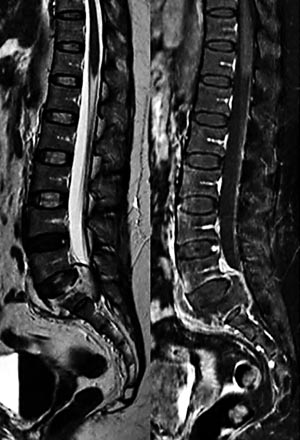

Pasient 2. Moren ble innlagt pga. smerter i begge hofteregioner med utstråling til tærne, og hun greide verken stå eller gå. MR av LS-columna viste abscess i virvelcorpus S1 med ekspansjon mot spinalkanalen (fig 1), og skjelettscintigrafi viste nedsatt aktivitet i samme område. Pga. lokalisasjonen ble det ikke gjort forsøk på punksjon, men det kom vekst av M tuberculosis i ekspektorat.

Pasient 3. Jente, 13 år gammel, ble innlagt pga. smerter i venstre skulder, slapphet, dårlig matlyst og feber i en ukes tid. Røntgen thorax viste mulig fortetning i venstre hilum. Skjelettscintigrafi viste aktivitetsoppladning i virvelcorpus L4 og L5. MR viste ødem i begge virvler, bilaterale psoasabscesser med lengde opptil 12 cm og prevertebral abscess (fig 2). Ved ultralydundersøkelse av halsen ble det påvist abscedering i flere lymfeknuter. Psoasabscessene ble drenert og M tuberculosis isolert fra pussprøver og bronkialskyllevæske (tab 3).

Ved nevroradiologiske problemstillinger, som hos pasient 2, er MR den beste bildediagnostiske metoden (ig). MR med kontrast er gullstandard ved spondylodiskitt. Kontrasten gir god fremstilling av abscesser intraossøst, i skiverom, eller pre- og paravertebralt, som hos pasient 3 (fig 2). Ultralydundersøkelse kan være nyttig ved bløtvevshevelse. Det ble funnet tegn til abscessdanning i bløtvev hos pasient 1, 3 og 5.